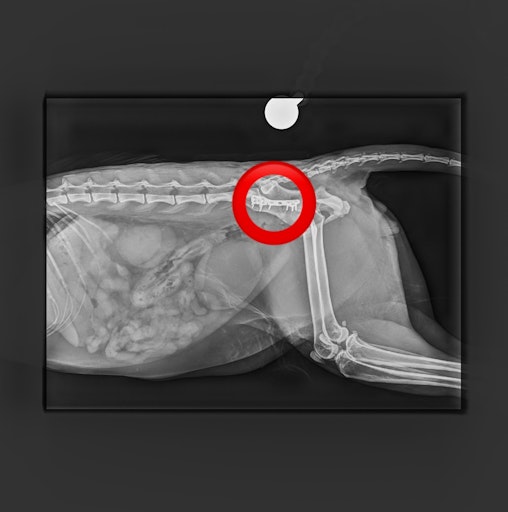

Kürzlich hat der Tierschutzhof Pfotenhilfe einen schwer verletzten Kater aufgenommen, der in Mondsee (OÖ) gefunden wurde und ihn unverzüglich zum auf orthopädische Chirurgie spezialisierten Tierarzt Mag. Daniel Eschlböck in Alkoven (OÖ) gebracht. Dieser hat auf den Röntgenbildern multiple Beckenbrüche festgestellt und bereits eine Seite operiert, jetzt folgt die zweite Operation. Die Verletzungen deuten auf einen Autounfall oder Sturz hin. Der Kater ist natürlich stationär bei ihm untergebracht.